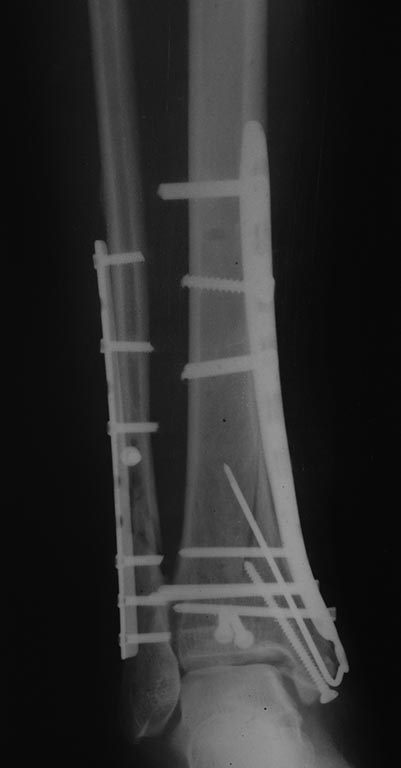

Дмитрий 19 Декабрь 2015, 00:55

Результат.

Считаю результат удовлетворительным, начали все-таки с м/берцовой, после её фиксации задний край встал. Вторым доступом был задне-медиальный здесь обнаружился не связанный с диафизом и значительный по величине метаэпифизарный передне- медиальный отломок, его временно фиксировал спицами, затем провёл фиксацию внутренней лодыжки к этому фрагменту также спице, задний край фиксировали винтами, далее медиальная пластина, м/инвазивно(насколько возможно), затем винт во внутреннюю лодыжку. После этого проверил синдесмоз, он оказался состоятелен. На счёт что это за перелом: если бы не один передне-медиальный фрагмент, который по-суть захватывает 40-50% суставной поверхности, то без сомнений это 4 4, а так все-таки 4 3, но синтез м/берцовой считаю в этом случае был необходимым и первоочерёдным ). P.S: спасибо всем за советы, очень помогло в планировании.

Это правильно, что с малоберцовой начали и фиксировали её. Задний край, медиальный отдел. Проверка стабильности-Все ок. Правда, медиальная лодыжка кажется недорепонировпнной.

Дмитрий, по снимку не понятно, какие винты какую функцию выполняют. Есть ли винты стягивающие? Если есть, то какие?

Отправитель: Дмитрий 19 Декабрь 2015, 20:32

По суставной отрепонирована была ad ocullus, на снимках может так смотреться в следствие оскольчатого характера, стягивающий винт в пластине 4,5 мм один. Не рискнул ставить стягивающие в "ложку" побоялся "раздавить".

Дмитрий 21 Декабрь 2015, 17:14

Результат операции.

Отправитель: Alexey Semenistyy 22 Декабрь 2015, 00:33

Выглядит вполне себе не плохо. Хотя, кое-что можно было бы сделать по-другому

Отправитель: Alexey Semenistyy 23 Декабрь 2015, 01:39

Дмитрий, моя тактика была ты точно такой же.

1) Даже если бы било чем м с кем, я бы не стал делать окончательный остеосинтез в день поступления. Перелом сложный (44С с претензией быть 43В), больная тучная, значит энергия травмы приличная, несмотря на непрямой ротационный главным образом механизм, и мягкие ткани могут быть скомпроментированы. В первые часы это оценить трудно, можно только предположить. Аккуратная, не грубая закрытая репозиция и наружный фиксатор в положении приблизительной репозиции - это то, что я сделал при поступлении, примерно так же как и вы и это сделали.

2) Я бы все делал в таком же порядке: малоберцовую и задний край, затем медиальный раскол, в последнюю очередь медиальную лодыжку. Оценка стабильности синдесмоза.

КТ, безусловно, показана, но только после репозиции и в аппарате

Иначе я бы поступил с направлением некоторых винтов, с их функцией (см вложение):

1)Винты, фиксирующие задний край, должны быть стягивающими, приходить перпендикулярно плоскости перелома.

2)Нужен хотя бы один стягивающий винт вне или через опорную пластину для вертикального метаэпифизарного раскола параллельно суставной поверхности (в прямой проекции) и достаточно близко к ней.

3) Винт через внутреннюю лодыжку также должен быть стягивающим. Направление и длину его я бы выбрал такое, чтобы он заканчивался не в зоне вертикального разлома, не в зоне перехода метафиза в диафиз, где в центре кости уже мало губчатого вещества, а более дистльно и вертикально , где "губка" более плотная. Возможно, стягивание петлей по Веберу здесь более предпочтительно.. Ну и с открытой репозицией медиальной лодыжки постарался бы...

3) В качестве опорной пластины для медиального раскола взял бы 1/3-трубки, ну в крайнем случае максимум 3,5 метафизарную LCP. "Ложка" тут избыточна, а вот стягивающего винта не хватает.

Отправитель: Paul 24 Декабрь 2015, 08:09

На ренгенограмме в сагитальной проекции контуры кортикальной пластинки внутренней лодыжки не совпадают - в месте перелома, а на сагитальной проекции, кажется, смещение внутренней лодыжки кпереди....

сергей 28 Декабрь 2015, 19:52

Интересно бы сделать снимки обоих голеностопов на одной кассете и посмотреть синдесмоз на здоровой конечности. Какое-то ощущение, что имеется небольшой подвывих...